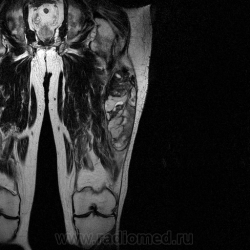

Ну вот аксиальные срезы, где то затерял =(

С учетом вашего опыта, мне кажется Вам и без дословной интерпретации МР-протокола будет все понятно.

Мой коллега в заключении указал о вероятней всего рабдолейомиосаркоме, если я ошибся то чуть позже поправлюсь.

Я тоже пока что в этом деле лось, но думаю дело поправимое, на днях улетаю С-Петербуг в МАПО(цикл КТ и МРТ), ну да ладно, что косается пациента то он ещё в 2007 году обращался по месту жительства к травматологу по поводу ушиба бедра с формированием гематомы, была назначена местная рассасывающая терапия, до 2009г. видимо ждали пока рассасется в декабре обратился к хирургу по поводу посинения и увеличения в объёме задней поверхности бедра, назначен гепарин в феврале был вскрыт абсцесс в этом месте, далее только в марте сподхватились по УЗИ-мягких тканей признаки образования, ну и открытая ножевая биопсия: Описание изменений, выявленных при микроскопическом исследовании: в материале фрагменты опухоли, представленной пучками вытянутых клеток с полиморфными гиперхромными, местами уродливыми ядрами. Определяется значительное количество митозов, встречаются поля некроза опухоли. При иммуногистохимическом исследовании опухолевые клетки экспрессируют виментин, отсутствует реакция на десмин, гладко-мышечный актин, S100. Патоморфологическое заключение: саркома мягких тканей, боее вероятно фибросаркома.